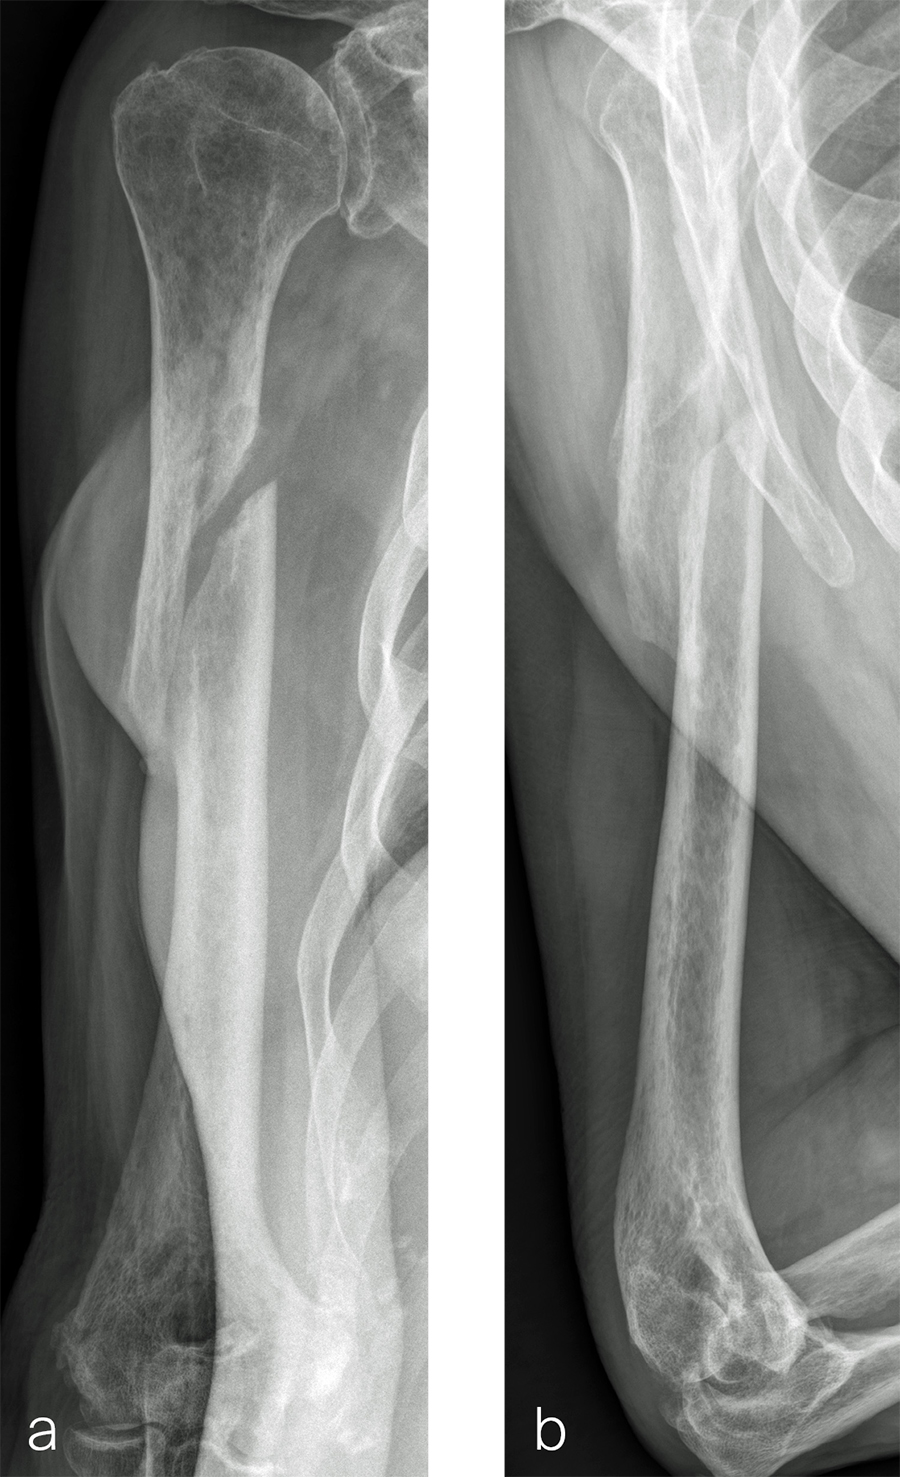

Case 2: RIA 2 use at the humerus (provided by Mark Lee, Sacramento, US)

The patient was an 83-year-old right-hand dominant man who sustained a closed right humeral shaft fracture approximately 10 months before presentation. He was not initially offered surgical care and was treated with functional bracing. The patient has moderate pain but mainly complains of instability and lack of strength in his right arm. He was offered surgical nonunion repair with autogenous iliac crest bone grafting but declined iliac crest harvest. X-rays showed oblique nonunion with resorption and confirmed diagnosis of pseudarthrosis (Fig 7).

After debridement and resection of the pseudarthrosis, we accessed the distal segment of the humeral canal and used a small caliber RIA 2 reamer head to harvest intramedullary bone graft (Fig 8) for final plate fixation (Fig 9).